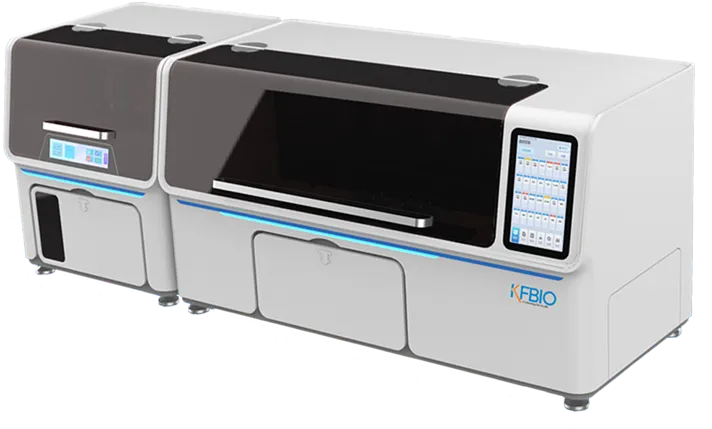

KF-FL-020

Digital Pathology 20 Slides Scanner (Fluorescence)

Fast, Stable, Clear

Scientific research, clinic, tumor microenvironment